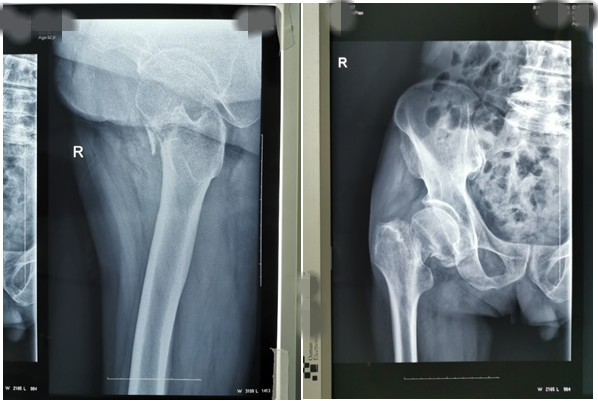

近期,我科又為兩位高齡老人因股骨頸骨折行髖關(guān)節(jié)置換術(shù)。一位是呂大爺,82歲高齡,右髖部外傷后疼痛一個月就診。當時呂大爺外傷后局部疼痛,未引起注意仍日常活動,癥狀逐漸加重后就診,既往有高血壓、腦梗塞、腦出血病史,入院后積極完善術(shù)前評估,在無絕對手術(shù)禁忌癥時行右側(cè)股骨頸骨折髖置換術(shù),手術(shù)時間短,出血少,術(shù)后第二天呂大爺扶助步器下床活動,避免了因骨折長時間臥床各種并發(fā)癥的發(fā)生,老人及家屬對我們的治療非常滿意。(見下圖)

右髖正側(cè)位手術(shù)前后對比圖